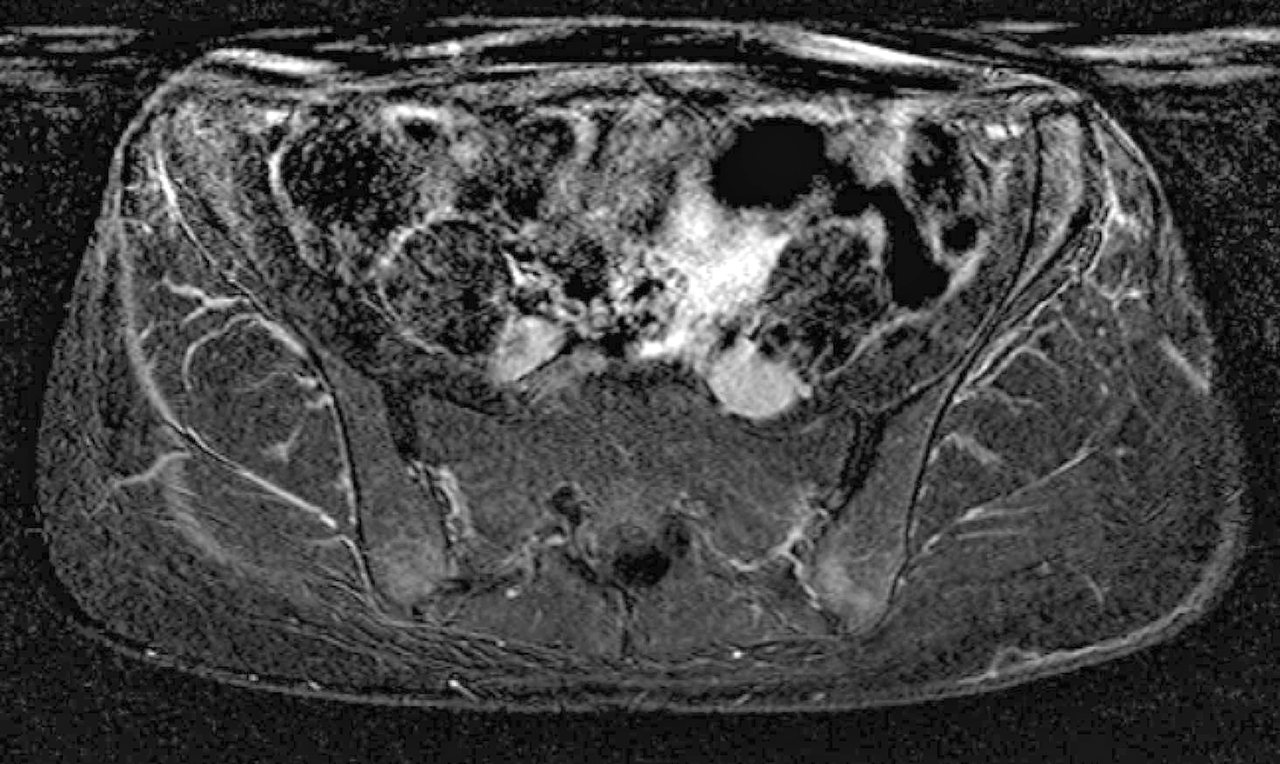

Das MRT des Beckens zeigt die Entzündung an den Sehnenansätzen des Os ilium auf beiden Seiten sowie ein Knochenödem im rechten Hüftkopf.  Das MRT des Beckens zeigt die Entzündung an den Sehnenansätzen des Os ilium auf beiden Seiten sowie ein Knochenödem im rechten Hüftkopf. © Härle P. Ärzteblatt Rheinland-Pfalz 2018; 71: 21 © Landesärztekammer Rheinland-Pfalz, Mainz

Die Arthrosono bestätigt die Coxitis rechts und links. Nach intraartikulärer Injektion von Triamcinolon plus Lokalanästhetikum ist die Frau sofort schmerzfrei. Leitliniengerecht startet man eine Basistherapie mit Methotrexat. Drei bis vier Wochen später wird die Patientin aber erneut mit Schmerzen vorstellig, dieses Mal diffus im Becken. Im MRT fallen enthesitische Veränderungen am Os ilium beidseits sowie ein Ödem im rechten Hüftkopf auf.

MRT des Beckens MRT des Beckens © Härle P. Ärzteblatt Rheinland-Pfalz 2018; 71: 21 © Landesärztekammer Rheinland-Pfalz, Mainz